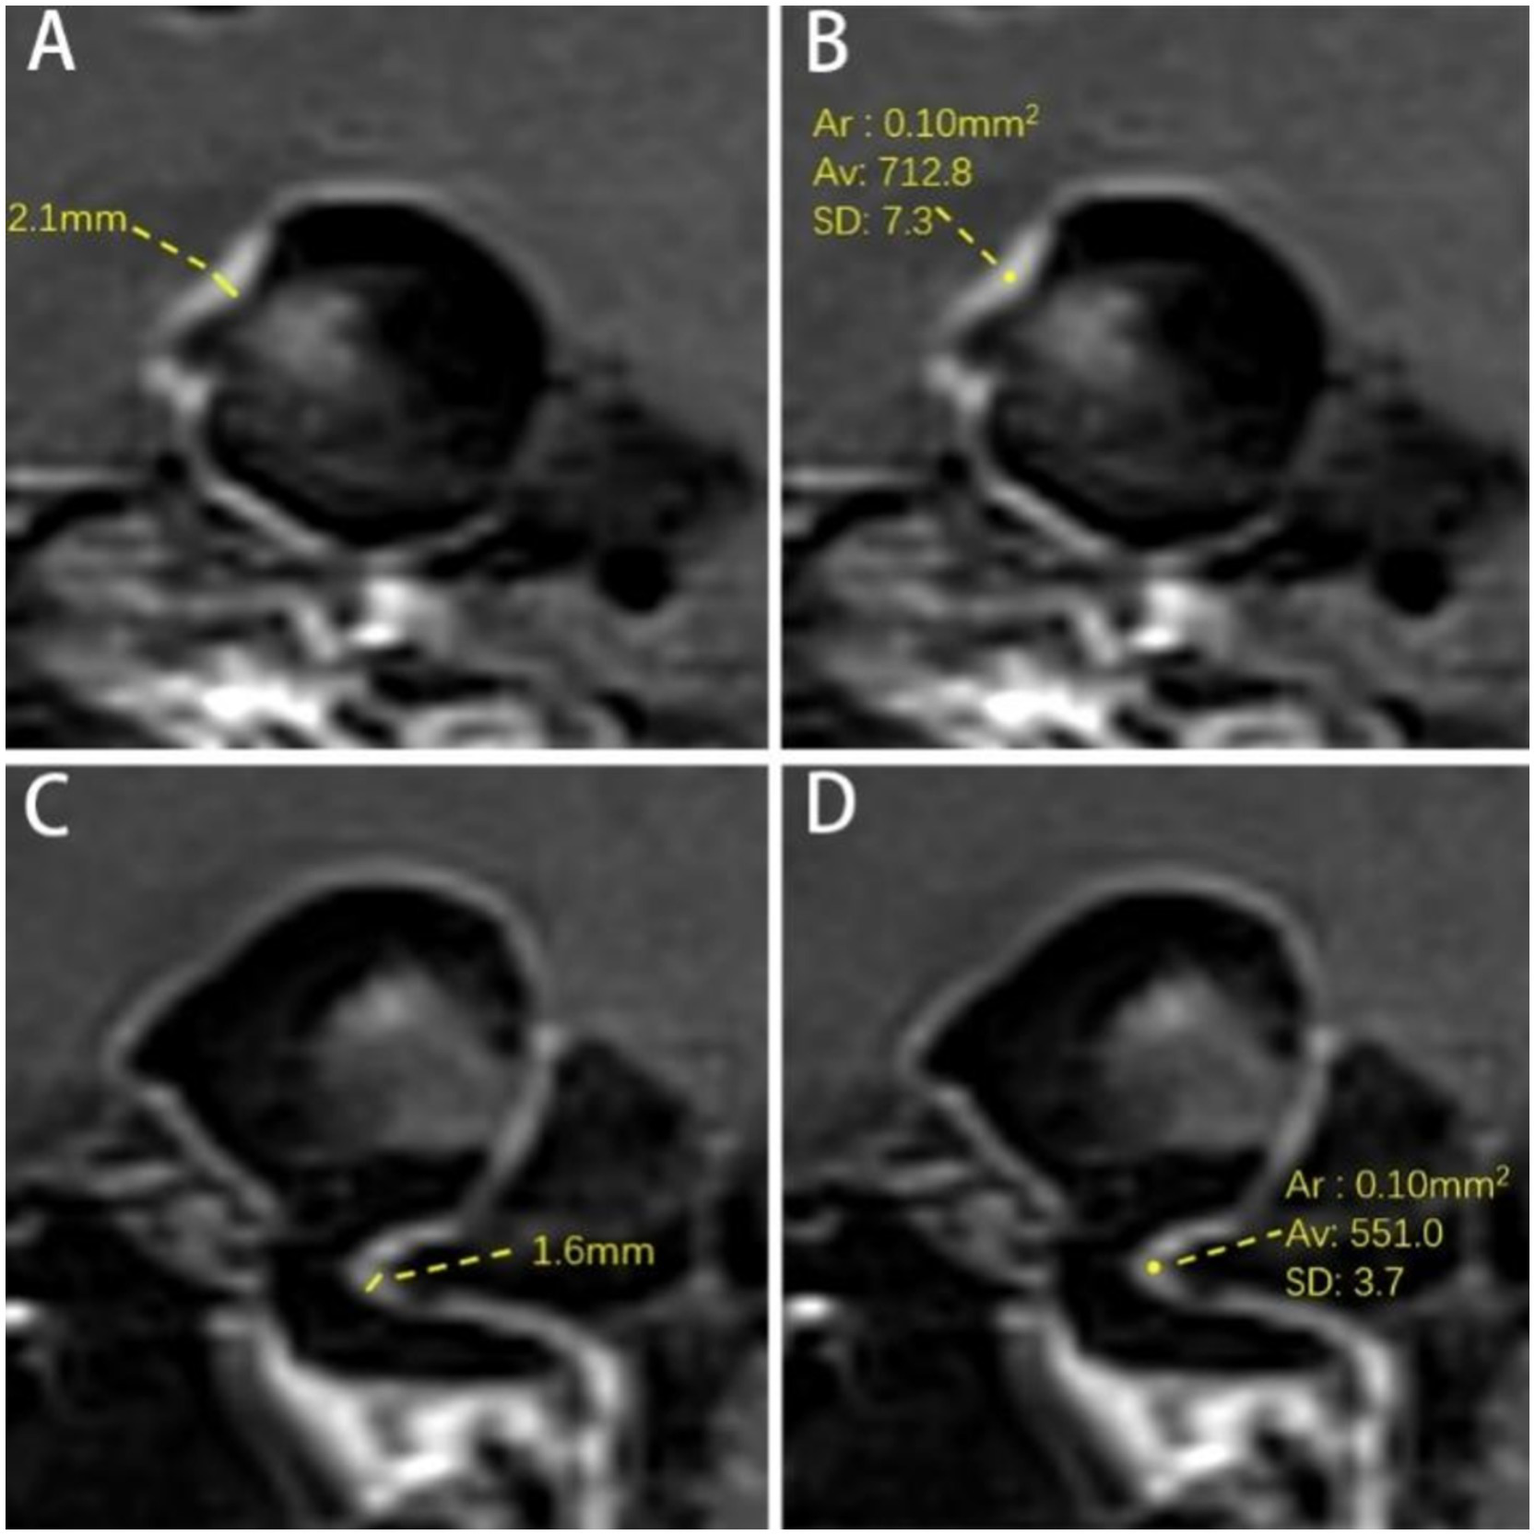

The thickest part of the aneurysm wall and the parent artery wall were measured three times at the direct boundary, and the average value was calculated as aneurysm wall thickness (AWT) and parent artery wall thickness (PAWT) (Figures 3A,C).

Figure 3

Measurement of aneurysm wall and parent artery. (A) Measurement of AWT. The AWT is 2.1 mm. (B) Measurement SI of AWE. The signal intensity of the aneurysm wall is 712.8. (C) Parent artery wall thickness (PAWT). The PAWT is 1.6 mm. (D) Parent artery wall signal intensity. The signal intensity of the parent artery wall is 551.0. Ar = Average Range; Av = Average Signal Intensity of ROI; SD = Standard Deviation.

The post-contrast SI of the aneurysm wall (SIAW(post)) and parent artery (SIPA(post)) was measured separately three times on post-contrast images on the layer of their respective maximum diameters, and the highest value was recorded as the enhanced SI (Figures 3B,C). Furthermore, the measurement range for parent artery was within 3 mm of the aneurysm neck. The region of interest (ROI) was 0.1 mm2. The pre-contrast SI of the aneurysm wall (SIAW(pre)) and parent artery (SIPA(pre)) was measured using the same method at the corresponding site. The SI of the right frontal white matter (SIRFWM) was measured as a reference on both pre- and post-contrast images. The ROI was 20 mm2. Additionally, the pituitary stalk SI (SIPS(post)) was measured three times on the upper, middle, and lower parts of the pituitary stalk on CE-HR-VWI images and the highest value among them was recorded. The ROI was 0.1 mm2 (18).